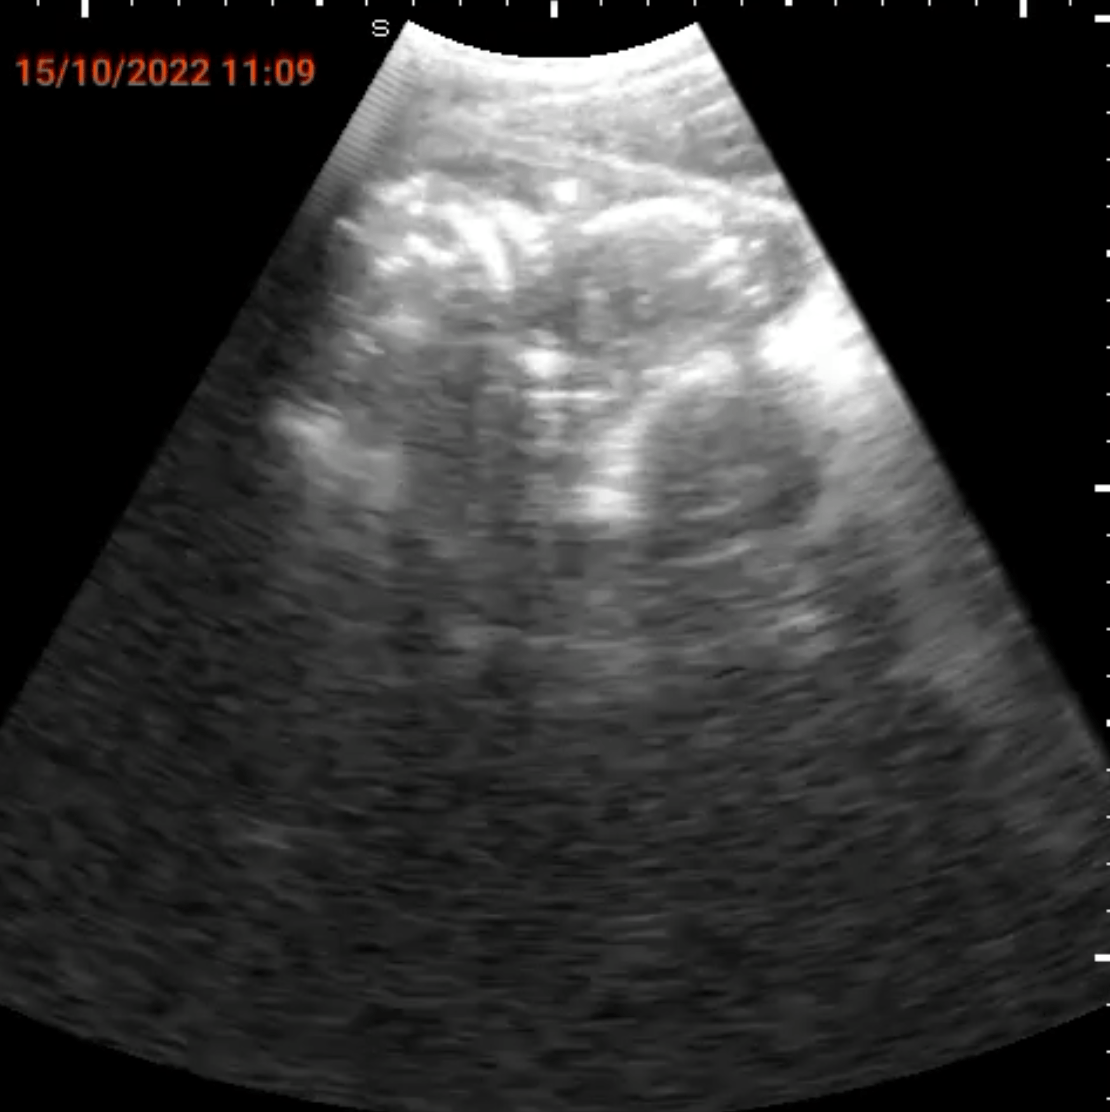

我々が、今回、マラウィに導入を目指しているのは、コンゴ民主共和国で確立された遠隔妊婦腹部エコー健診システムSPAQです。携帯電話にプローブを接続し、腹部エコー検査ができるシステムで、訓練を受けた看護師が操作をすることができ、かつインターネットで中央病院の医師と画面を共有することができます。トレーニングを受けた看護師が地域に出かけて妊婦の腹部エコー健診を施行し、異常が発見された場合には、中央の医師が画像を共有し、診断・緊急手術指示等の対処をすることができます。我々はこの医療システムの確立と共に、ソーシャルビジネスの手法を取り入れて、医療システムのサステイナビリティを得ることを目指します。